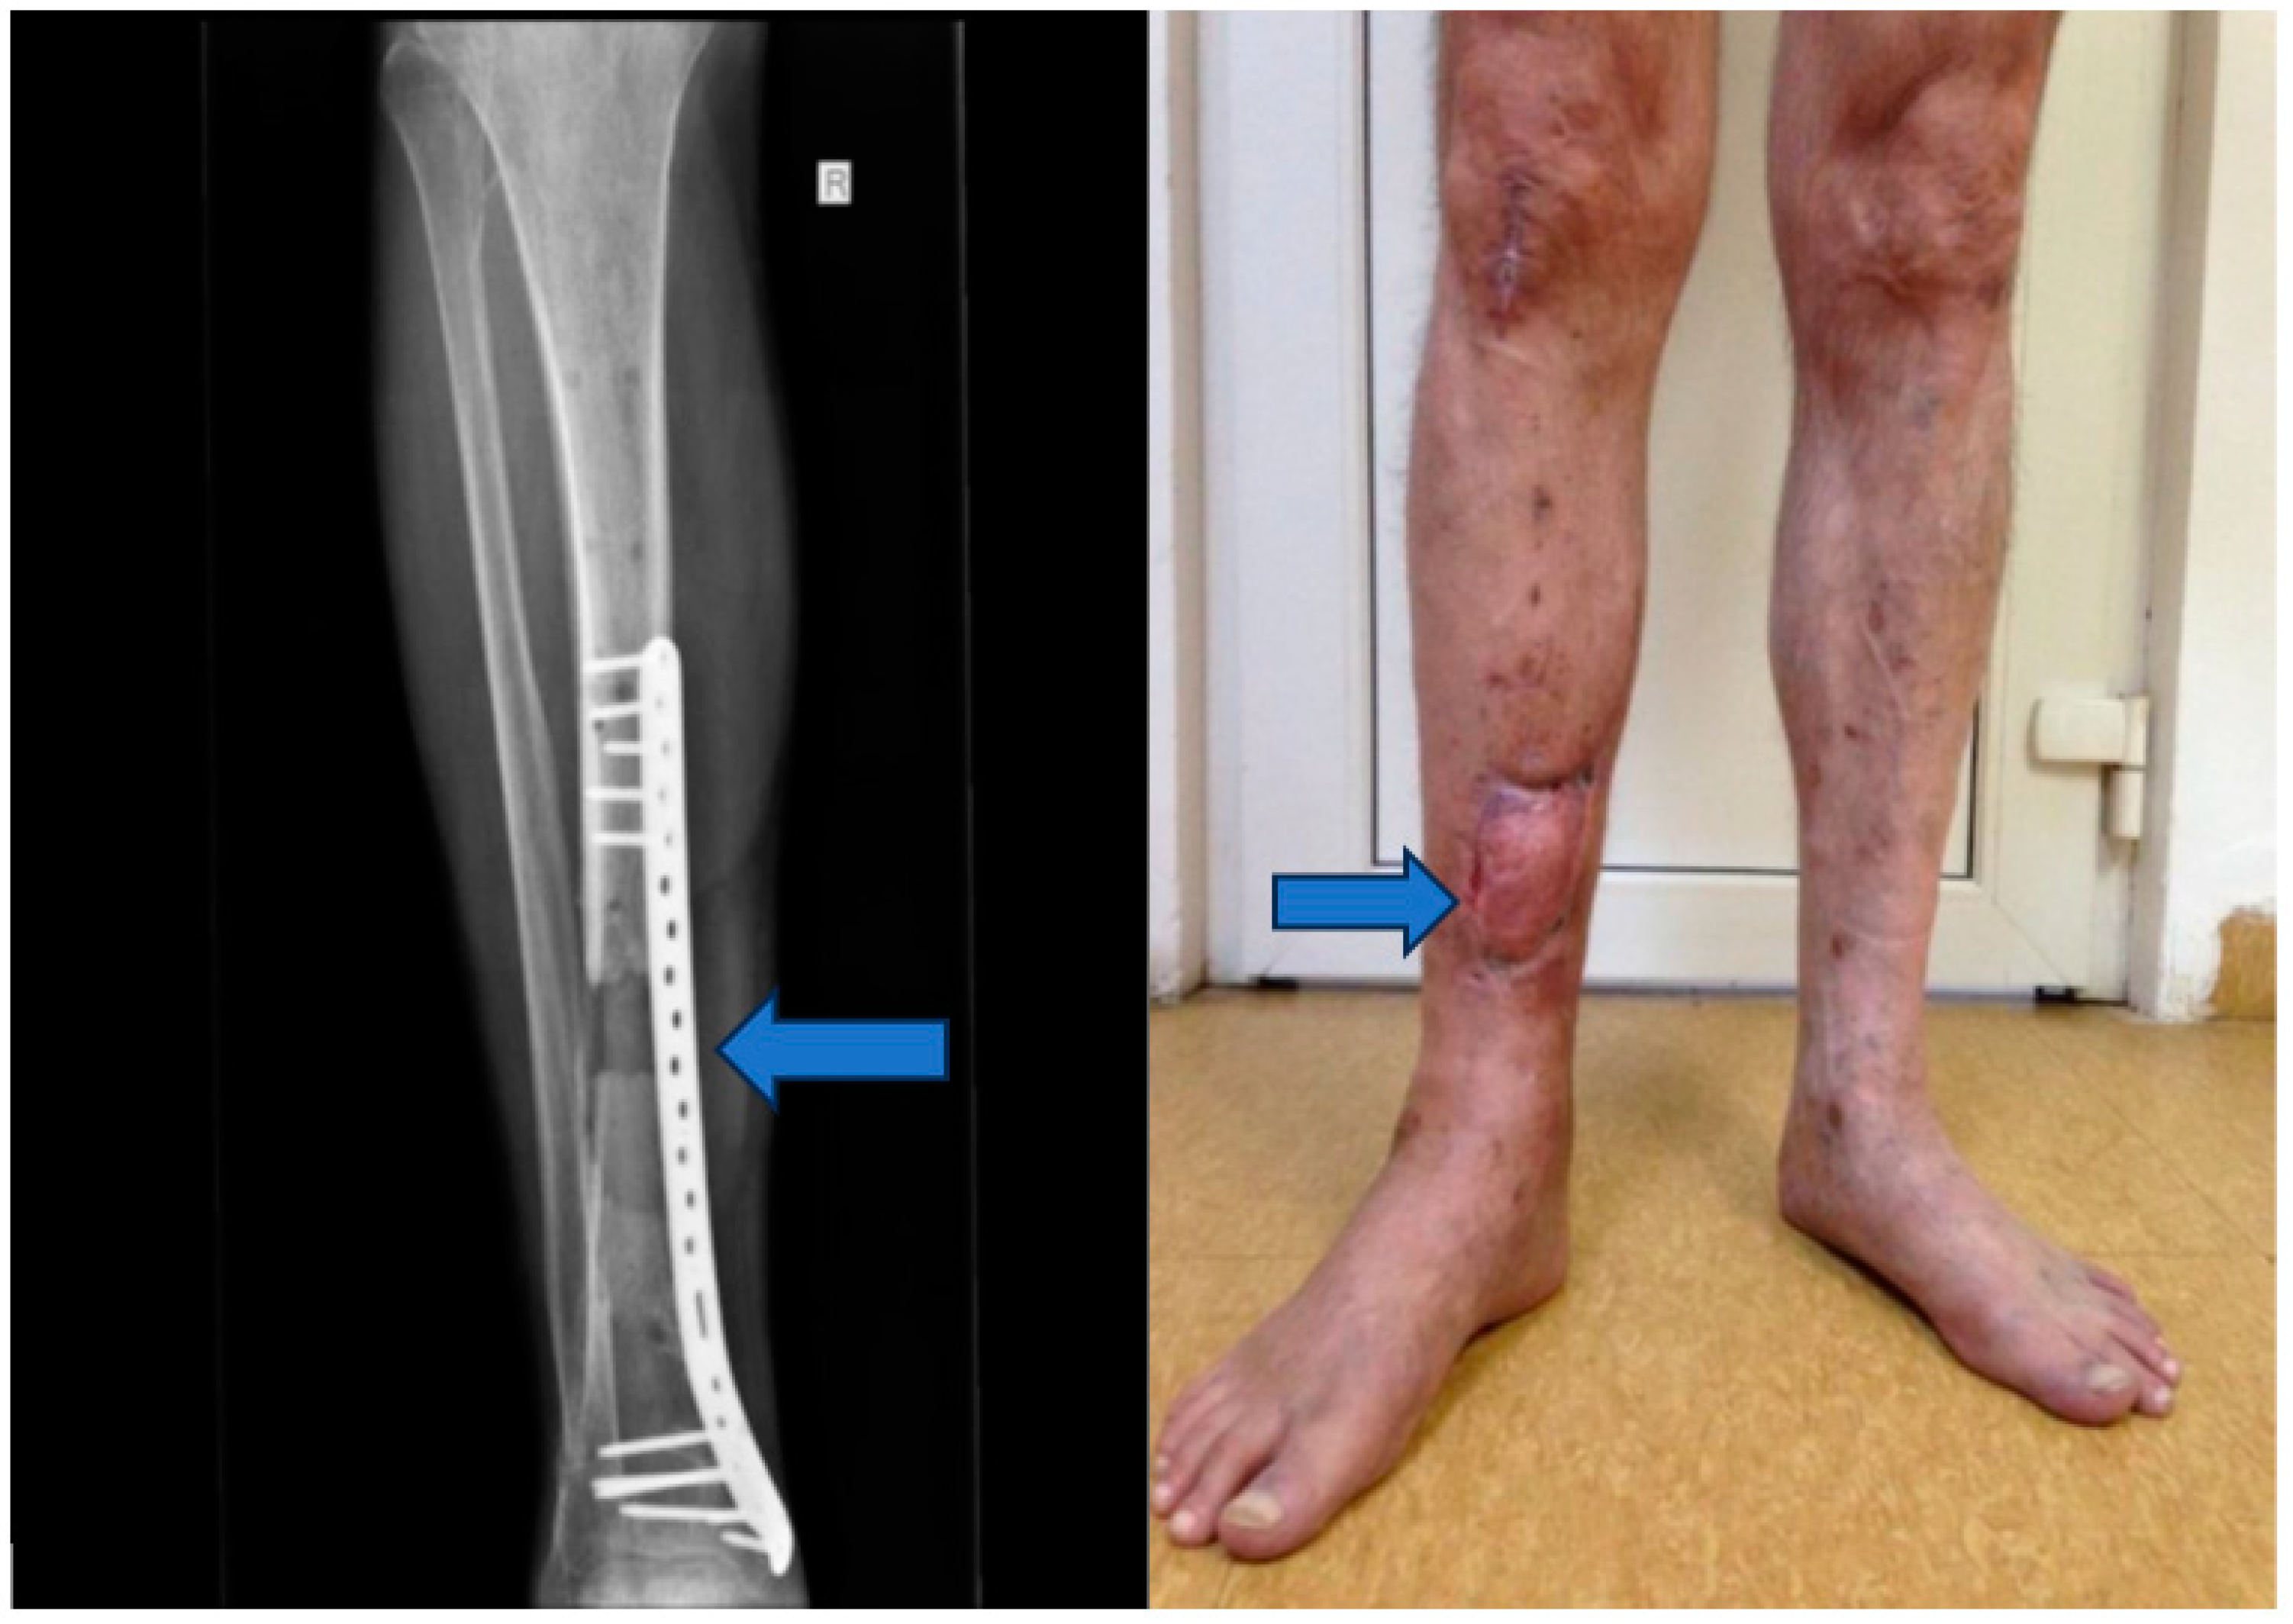

Stage 3: Grafting for osteo-muscular defect (Figure 5).

Objective: To address the osteo-muscular defect and facilitate tissue regeneration.

Methods: This stage involved grafting the osteo-muscular defect using autografts harvested from the rib and serratus anterior muscle. The external fixation device was maintained to provide support during the graft integration period.

Stage 4: Flap integration and internal fixation (Figure 6).

Objective: To ensure the integration of the musculocutaneous flap and provide internal fixation to stabilize the tibia.

Methods: After an 8-week integration period, the musculocutaneous flap was deemed stable. The external fixator was removed, and internal fixation was achieved using a blocked Less Invasive Stabilization System (LISS) plate, which was inserted utilizing the Minimally Invasive Plate Osteosynthesis (MIPO) technique.

Figure 5. Osteo-muscular defect.

Figure 6. Musculocutaneous flap and internal fixation was achieved using a blocked Less Invasive Stabilization System (LISS) plate.